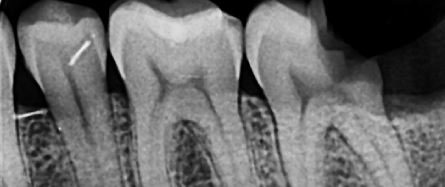

Radiographic Examination :

Radiographs and clinical pictures during the treatment :

Master cone GP PA

Post-op xray.

Treatment Procedure and Radiographic Documentation

Radiographs and clinical pictures were taken during treatment, including:

• Master cone GP periapical radiograph

• Post-operative X-ray